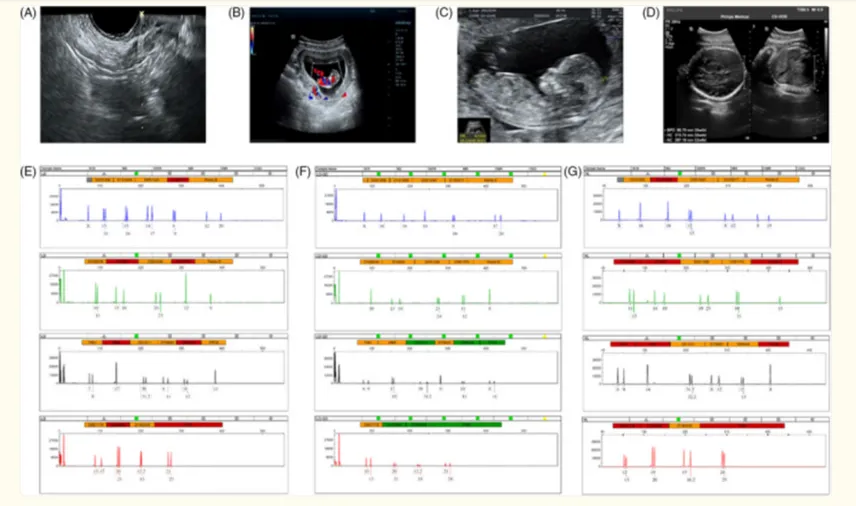

图片来自文献1

目前全球范围内,已经有多项涉及人类受试者的临床研究。以下表格摘取了部分干细胞治疗卵巢早衰的临床试验汇总了所使用的给药途径、细胞剂量以及临床主要观察结果,总共涉及到150余名患者。

研究人员选取了包括促卵泡激素 (FSH)、怀孕和活产次数、雌二醇 (E2)、卵泡计数和卵巢重量等作为判断卵巢功能恢复的可靠预测指标,并且发现,在干细胞疗法治疗后,这些指标存在着明显改善。